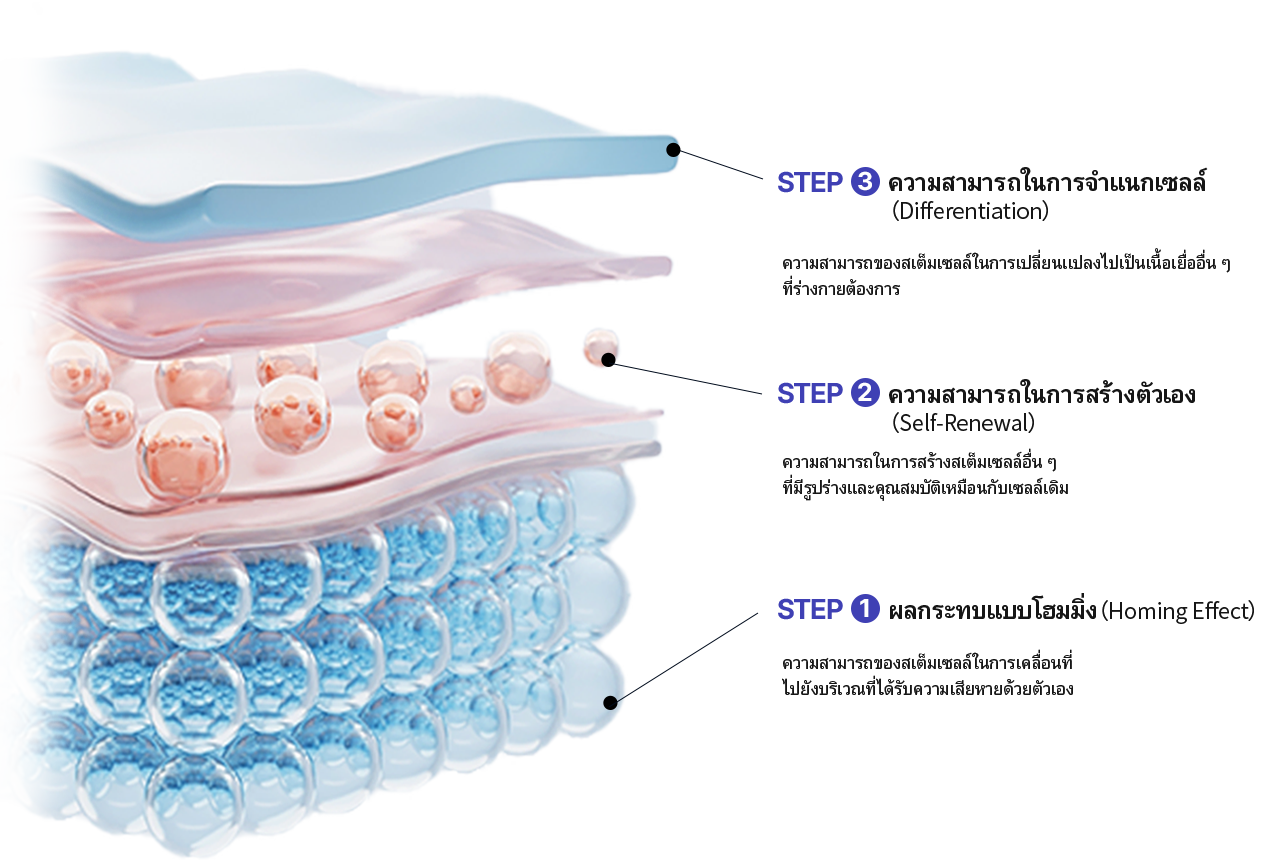

ลดความหย่อนคล้อย

ลดความหย่อนคล้อย